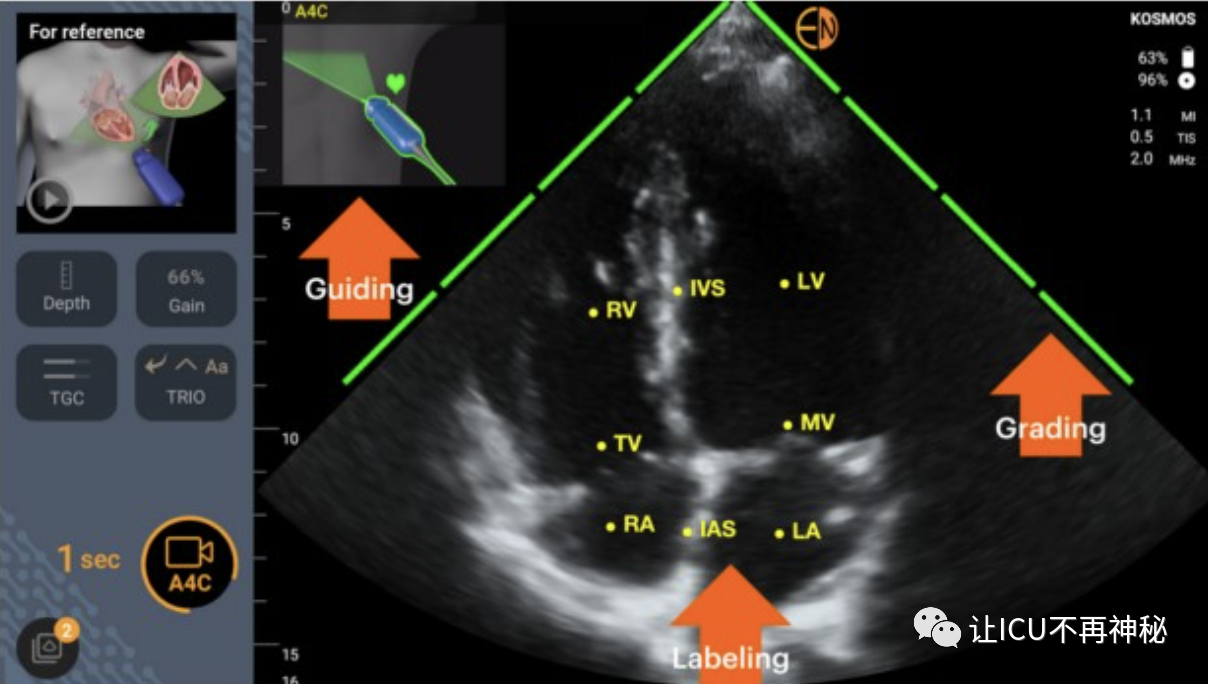

人工智能與治療點(diǎn)超聲心動(dòng)圖已經(jīng)訓(xùn)練了幾種ML算法來(lái)識(shí)別心臟圖像,并引導(dǎo)用戶正確握住和定位他們的經(jīng)胸探頭。這樣的算法還能夠?qū)D像質(zhì)量進(jìn)行分級(jí)并標(biāo)記心臟結(jié)構(gòu)。圖1中顯示了一個(gè)示例。一些ML算法可以自動(dòng)進(jìn)行超聲心動(dòng)圖測(cè)量。例如,autoVTI算法可以識(shí)別心臟的5腔心尖視圖,在左心室流出道中自動(dòng)定位脈搏波多普勒卡尺,并在短時(shí)間窗口內(nèi)記錄主動(dòng)脈下速度時(shí)間積分(VTI)(圖1)。最近的一項(xiàng)臨床評(píng)估表明,autoVTI算法可以幫助受訓(xùn)者像超聲心動(dòng)圖專家一樣高效地使用超聲波估計(jì)VTI、腦卒中量(SV~VTI x Pi)和心輸出量。還開(kāi)發(fā)了幾種ML算法用于左心室射血分?jǐn)?shù)(LVEF)的自動(dòng)估計(jì)。比較研究表明,與專家手動(dòng)測(cè)量相比,它們可以使新手更準(zhǔn)確、更具再現(xiàn)性地測(cè)量LVEF。其他超聲算法已被設(shè)計(jì)為通過(guò)下腔靜脈呼吸變化的自動(dòng)量化來(lái)預(yù)測(cè)機(jī)械通氣患者的流體反應(yīng)性,或通過(guò)肺B線的自動(dòng)量化檢測(cè)肺水腫。總之,ML算法在幫助新手進(jìn)行治療點(diǎn)超聲心動(dòng)圖評(píng)估方面的價(jià)值已在幾項(xiàng)臨床研究中得到證明。然而,鑒于接受過(guò)超聲心動(dòng)圖培訓(xùn)的重癥監(jiān)護(hù)醫(yī)生的比例正在急劇增加,人工智能創(chuàng)新是否有必要增加超聲血流動(dòng)力學(xué)評(píng)估的數(shù)量和質(zhì)量仍有待確定。